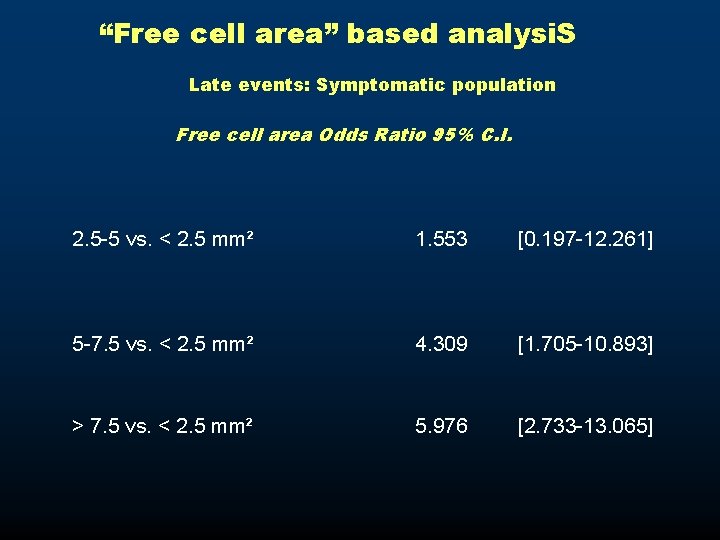

“Free cell area” based analysi. S Late events: Symptomatic population Free cell area Odds Ratio 95% C. I. 2. 5 -5 vs. < 2. 5 mm² 1. 553 [0. 197 -12. 261] 5 -7. 5 vs. < 2. 5 mm² 4. 309 [1. 705 -10. 893] > 7. 5 vs. < 2. 5 mm² 5. 976 [2. 733 -13. 065]